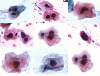

Patients with an oral epithelial abnormality that appeared clinically benign- minimally suspicious- and did not have an obvious etiology such as trauma or infection were prospectively enrolled in the study (Figure 1). The inclusion and exclusion criteria for patients enrolled in the study are summarized in Table 1.

Figure 1. Clinical examples of minimally suspicious lesions sampled.